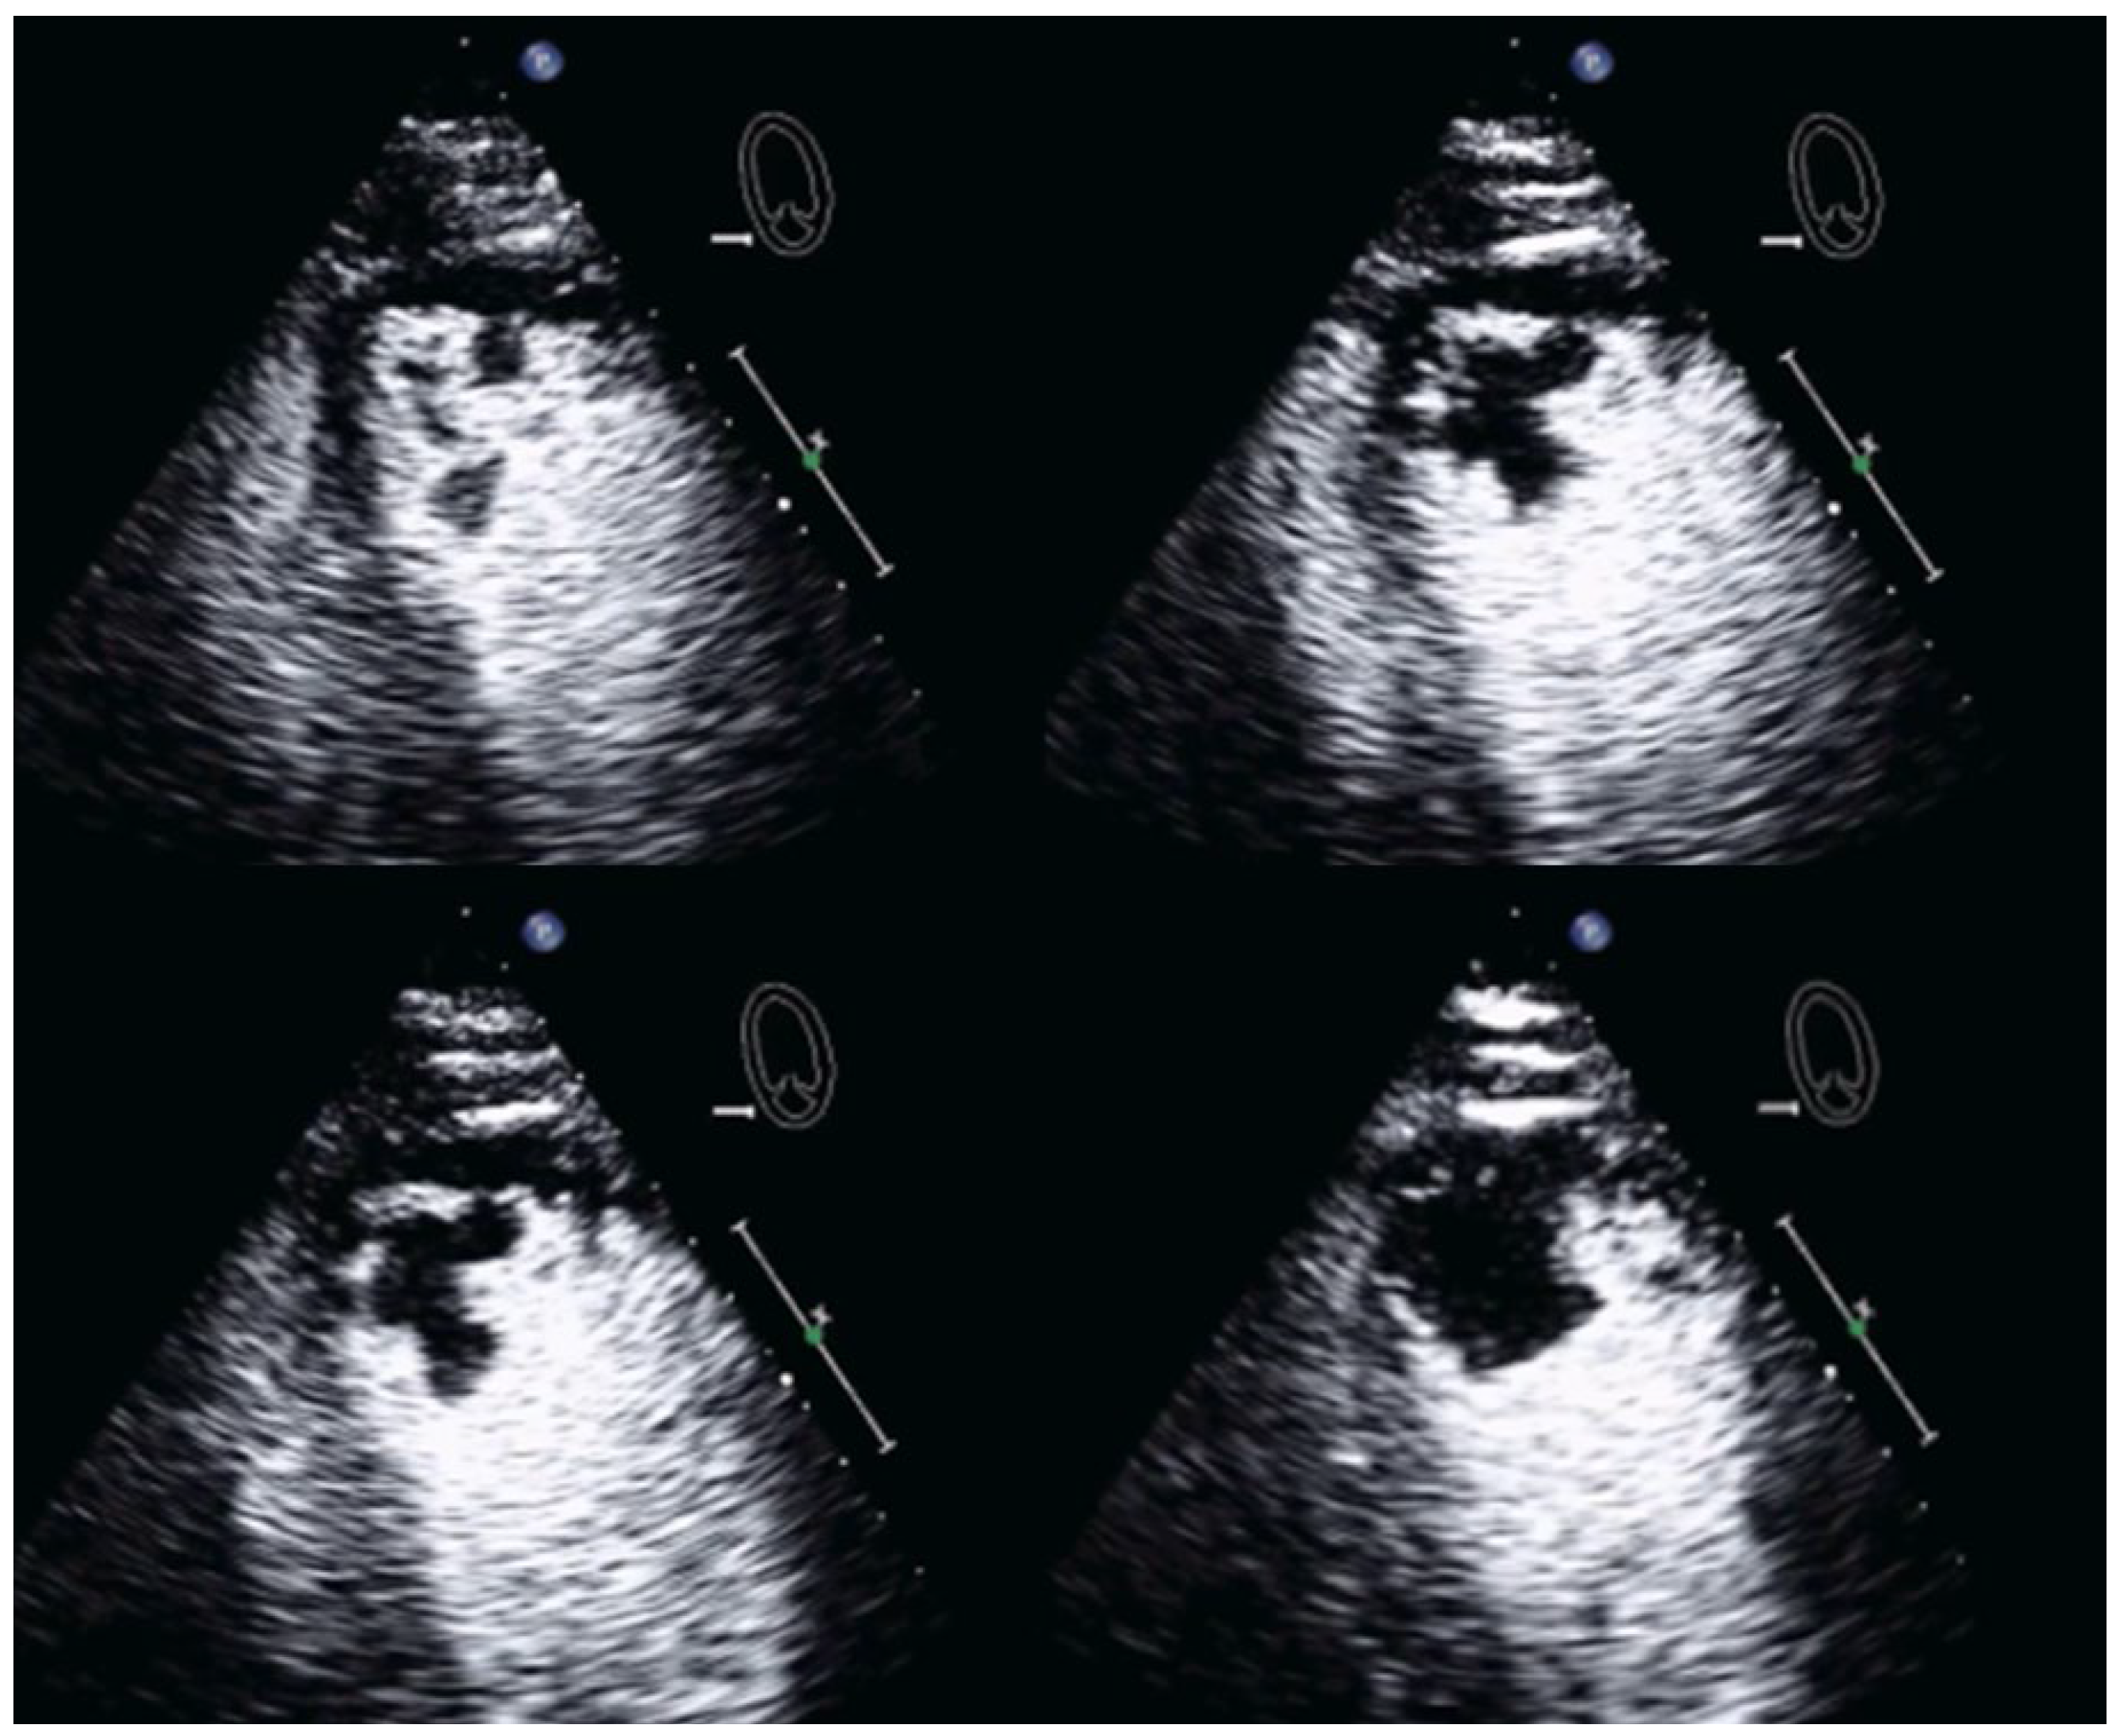

| Imaging method | Low-MI-contrast-specific imaging and intermediate-MI-contrast-specific imaging |

| Imaging planes | standard apical views additional zoomed views sweeps through the region of the suspected thrombus |

| Sector depth/width | Entire LV + 1/3 LA to assess global/regional LV function, zoomed views of the region with the suspected thrombus |

| Focus | At the depth of the suspected thrombus |

| Gain | Adjust to avoid obscuring the thrombus by intensive opacification of the cavity |

| Contrast application | bolus injections |

| Typical findings | 1. echofree mass 2. present in two different imaging planes 3. lump or laminar shape different from trabeculations’ documented size (two orthogonal diameters in at least one of the views), location, type (laminar vs. lump, single vs. multiple), surface (smooth vs. irregular) and mobility |